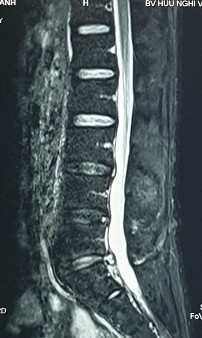

2. Hình ảnh khảo sát dẫn truyền thần kinh, điện cơ đồ và MRI (thực hiện trên mẫu nghiên cứu: bệnh nhân Hoàng Đình H., mã số bệnh nhân 1010320).

Bệnh nhân H., khi khám lâm sàng có biểu hiện tổn thương rễ thần kinh L4, L5, S1. Kết quả xét nghiệm điện cơ thấy: dẫn truyền thần kinh thấy mất phản xạ H, nhưng kết quả khi điện cơ kim có biểu hiện tổn thương rễ thần kinh L5 . Kết quả chụp cộng hưởng từ là tổn thương thoát vị L4 – L5, L5 – S1. Như vậy, trên bệnh nhân này vị trí tổn thương thực tế khi kết hợp phối hợp giữa khám lâm sàng, chẩn đoán hình ảnh và chẩn đoán chức năng là vị trí rễ thần kinh L5.

Hình ảnh thoát vị đĩa đệm trên phim chụp MRI.